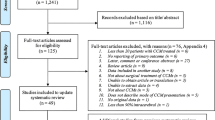

A single-centre, retrospective cohort study was performed, of all CCMs identified by searching a radiological imaging database for terms related to CCM between 1 January 2007 and 1 January 2019. The study was approved by the local hospital audit committee. Adults ≥18 years diagnosed with at least one CCM, confirmed by a board certified neuroradiologist during the study period, were eligible for inclusion. Patients with any spinal CCMs (excluding patients with coexisting brain CCM), absence of confirmed radiological diagnosis, and incomplete health records/follow-up data were excluded. The study setting was a tertiary neuroscience centre in England, UK, with a catchment area of approximately 3.5 million people. Patients were identified from coding lists from the centre’s radiology department, searching for ‘cavernoma’, ‘CCM’, and ‘cavernous malformation’.

Incidence of haemorrhage rate was calculated at the lesion level. Prognostic factors for symptomatic haemorrhage were delineated using stepwise multivariate proportional hazard regression analysis, incorporating variables with P values ≤0.1 on univariate analysis. A P value of <0.05 on multivariable analysis was considered significant. Analysis of haemorrhage predictors was completed on both per-patient and per-lesion level, to ascertain any differences between the two groups [16]. We investigated the proportional hazard assumption of both per-patient and per-lesion model by using Schoenfeld residual plots.

A total of 161 haemorrhages occurring in 148 CCMs were recorded, of which 136 (84.5%) occurred at presentation, and 25 (15.5%) during follow-up (Fig. 1). Including all CCMs, the annual haemorrhage rate was 1.00% per lesion-year (25 events in 2512.25 lesion years). Of the haemorrhages, 20% (N = 5) occurred within the first year of presentation, with 80% (N = 20) occurring between 12 and 180 months after diagnosis. CCMs presenting with symptoms (seizures, headache, or other symptoms due to haemorrhage at presentation) exhibited a haemorrhage rate of 1.50% per lesion-year (392 CCMs, 22 events in 1464.58 lesion-years), compared to CCMs that presented asymptomatically with a rate of 0.29% (352 CCMs, 3 events in 1047.67 lesion-years, P < 0.001) (Fig. 2).